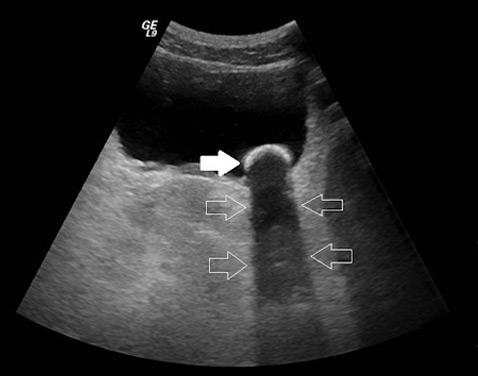

Hepática y vías biliares

El objetivo es visualizar el estado del hígado, vesícula biliar, páncreas y los conductos cístico y colédoco; esta ecografía puede diagnosticar enfermedades como, adenomas, quistes, tumores del páncreas, pancreatitis, cálculos y tumores de la vesícula y vías biliares, colecistitis, entre otras.

Abdominal

Es una prueba que se utiliza para examinar los órganos internos del abdomen, como hígado, bazo, vesícula biliar, páncreas, riñones y la aorta abdominal.